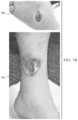

FIG.5, collectively illustrates a wound image before and after conversion to the CMYK space.FIG.5A shows a RGB image of a freshly debrided wound506 located on the lower calf and ankle of a patient.FIG.5B shows the imaged wound following conversion of the image to the CMYK space, illustrating the CMYK decomposition of the wound image. In such a CMYK decomposition,view512 shows the image in the cyan space,view516 shows features of the wound in the magenta space,view520 highlights aspects of the wound in the yellow space, and view524 shows the image of the wound in the black space. As shown inview512 ofFIG.5B, thewound506 does not contribute to the Cyan channel. On the other hand, the Magenta and Yellow channels illustrate how alternate color representations may highlight specific attributes of the appearance of thewound506, as shown inview516 andview520, respectively, ofFIG.5B.